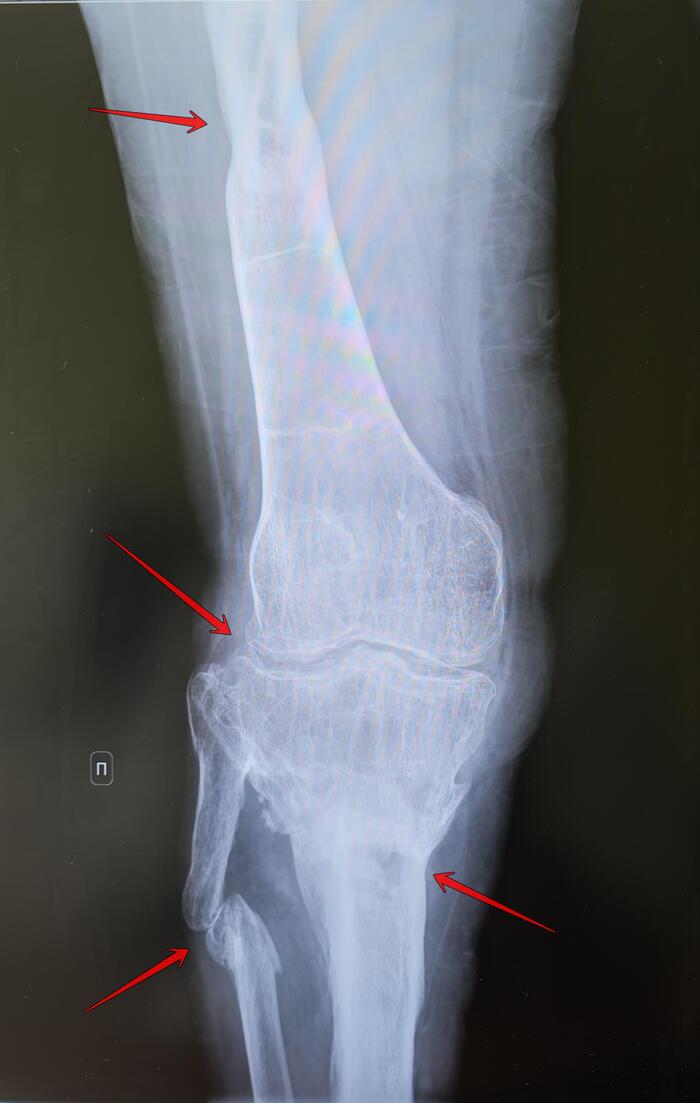

Остеомиелит, ложный сустав, гонартроз⁠⁠

В анамнезе ДТП, с последующим развитием остеомиелита, представленные снимки спустя 3 года с момента получения травмы.

На Р-граммах правого коленного сустава в 2х проекциях: неравномерное сужение суставной щели коленного сустава до 2 мм., дефигурация щели сустава, краевые остеофиты. Не сросшийся перелом в/3 диафиза малоберцовой кости со смещением отломка по ширине на 2 см. Проксимальный метаэпифиз большеберцовой кости выраженно деформирован, с участками лизиса костной ткани, структура костной ткани с участками остеосклероза/разряжения. В средней трети диафиза бедренной кости-сформированная секвестральная полость размером 13х7мм,с участком остеосклероза по переферии. Периостальная реакция бедренной, б/б костей. Заключение: Хронический остеомиелит правой бедренной, большеберцовой костей вне обострения. Не сросшийся перелом(ложный сустава) малоберцовой кости. Гонартроз справа 3 ст. по Kellgren

Категория годности - 565 постановление, ст.65а-Д:не годен к военной службе, направлен на прохождение МСЭ, получение группы инвалидности.